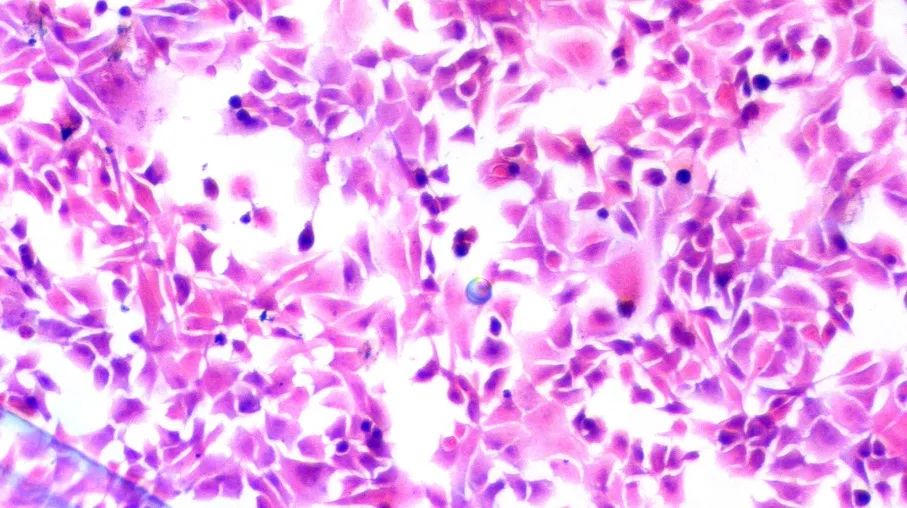

※实验结果示例:

正常情况下,苏木素染细胞核为蓝色,细胞质着色为粉红色。

,经第8次传代后,平滑肌细胞仍生长迅速,未见衰老迹象。倒置显微镜下观察均呈“谷和峰”样结构(图1 对照组2周的细胞;图2 实验组培养2周的细胞)。细胞爬片HE染色见膀胱平滑肌细胞细胞核呈两端钝圆的卵圆形平滑肌细胞核型。电镜检查可见平滑肌细胞密班结构。免疫组化染色检测α-actin呈阳性反应。从细胞爬片HE染色和免疫组化染色检测α-actin呈阳性反应中我们发现该方法所的膀胱平滑肌细胞的纯度几乎99%。 图1 对照组2周的细胞图2 实验组培养2周的细胞